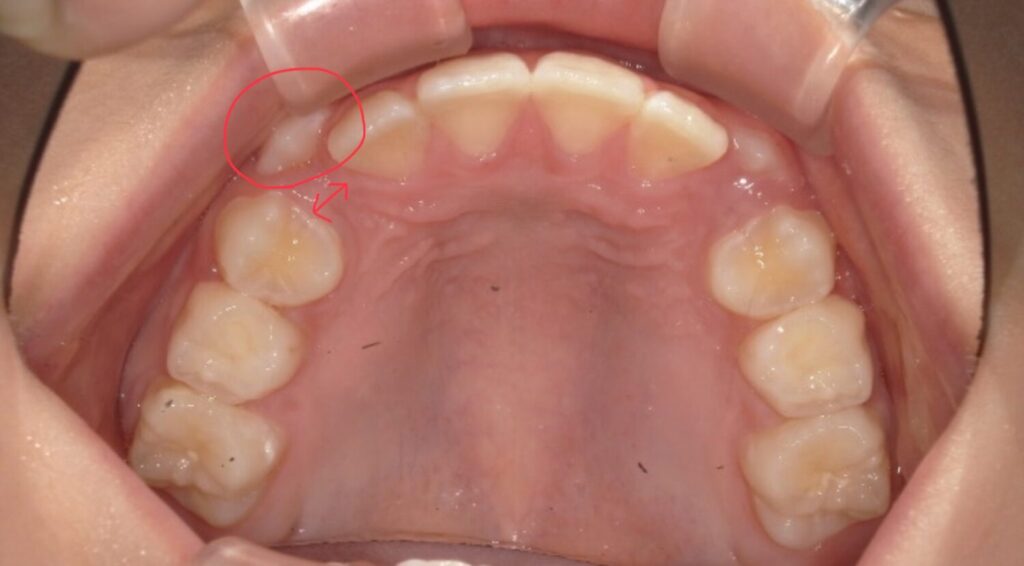

併用する装置

bwsの装着

マウスピースとアクティビティーをしている中で併用する装置があります。

舌のお手伝いをしてくれます。

またマウスピースも一緒に使うことができるのでとてもいい装置です。

初めにつけた時は上顎に少しの違和感は感じますがみんなすぐに慣れてくれます。

歯が少しずつアーチの方によっています。

ここまでくれば綺麗にアーチの中に入れそうなので装置も外しています。

長く使わないことも併用装置のメリットです。